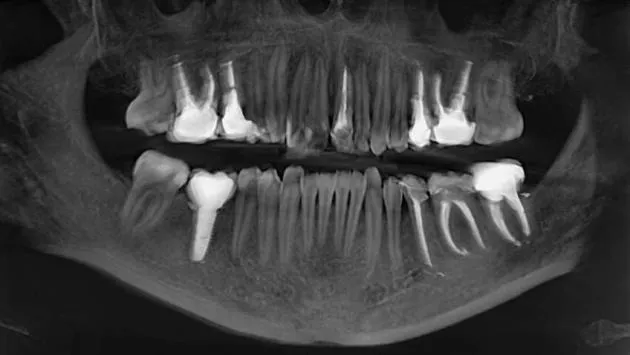

Вчені заявили, що люди в недалекому майбутньому зможуть вирощувати нові зуби замість імплантів. Така технологія вже проходить експериментальні випробування і може назавжди змінити стоматологію. Якщо раніше єдиним варіантом втрати зуба було встановлення металевих імплантів або знімних протезів, то тепер мова йде про можливість відновлення власних тканин пацієнта – природним шляхом.

Про це повідомляє “Popular Mechanics”. Дослідники створили гідрогель, який імітує середовище росту зуба, де клітини взаємодіють між собою і починають формувати структури, схожі на природні. За словами авторів проєкту, це відкриває шлях до створення зачатків зубів, які з часом можуть доростати безпосередньо в щелепі людини. Вчені вже виростили експериментальні зразки з корінням і емаллю, використовуючи клітини ясен людини та клітини мишей.

Схожі дослідження тривають і в Японії. Там компанія Toregem Biopharma вже готує перші клінічні випробування препарату, який активує “сплячий” ген росту зубів. Якщо результати будуть успішними, до 2030 року з’явиться ліки, здатні стимулювати ріст нового зуба після втрати постійного.

Фактично, це означає, що медицина переходить від протезування до біологічного відновлення. Замість штучних імплантів, які з часом зношуються або відторгаються організмом, людина зможе “виростити” власний зуб – з нервами, емаллю і коренем.